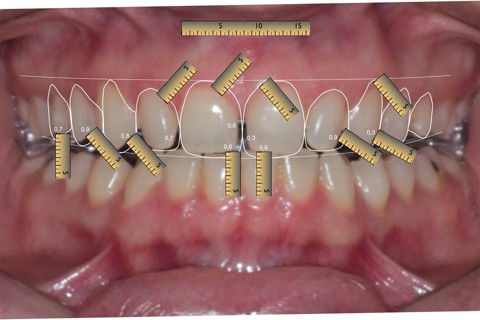

Digital Smile Design - DSD

1º Passo: Planejamento Digital Smile Design – DSD + Enceramento Diagnóstico;

2º Passo: Teste Drive estético/funcional através do Mock Up + Aprovação do plano de tratamento;